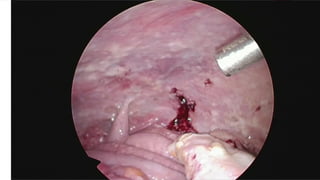

LAPAROSCOPY

 Diagnostic

 Staging